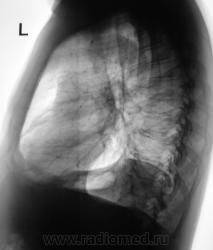

Легкие без очаговых и инфильтративных изменений, увеличены в объеме и прозрачности (эмфизема). Особенно увеличен объем язычковых сегментов левого легкого, несколько уменьшена в объеме нижняя доля. Левый купол диафрагмы расположен несколько выше нормы, особенно задние отделы, плевро-диафрагмальная спайка, увеличено расстояние до газового пузыря желудка. Предварительное заключение: подозрение на нарушение бронхиальной проходимости в левом легком, базальный гидроторакс слева. Дообследование: линейная томография (боковая проекция обязательна, может быть очень информативной), латерография для исключения/подтверждения свободной жидкости в левой плевральной полости.

Легкие без видимых очаговых и инфильтративных измнений. По прямой рентгенограмме левая половина диафрагмы расположена выше обычного. Прозрачность левого легочного поля выше правого. При изучении левой боковой рентгенограммы нижняя доля левого легкого резко уменьшена в объеме в пределах анатомических границ. Затенение базальных отделов левого легочного поля на фоне которого не дифференцируется левая половина диафрагмы. Викарная эмфизема верхней доли левого легкого.

Заключение(вывод): больше данных за ателектаз нижней доли левого легкого (гиповентиляция). Необходимо дополнительное исследование проходимости бронхиального дерева левого легкого. Бронхоскопия, ТМГ, КТ.